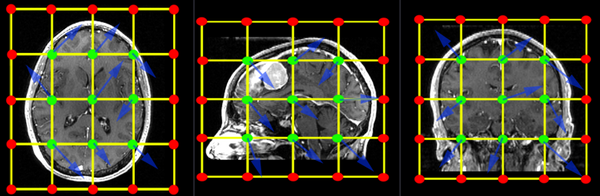

The BSpline grid is the basic structure of the deformation model applied when transforming one image to match the other. A uniform grid is placed over the entire image and the grid-points are allowed to move freely. These node displacements are then interpolated over the remainder of the grid. The image below shows an example of a 3x3x3 grid. An additional row of grid points is created at the boundary of the image (red). Those points are locked and do not move. They provide a boundary constraint to keep the grid from shifting. The interior points (green) are free to move in any direction (blue arrows), which gives 3 degrees of freedom (DOF) per grid-point. So a 3x3x3 grid translates into a transform with 27 DOF, a 5x5x5 grid will have 125 DOF. For comparison a rigid transform has 6 DOF, an affine transform has 12.